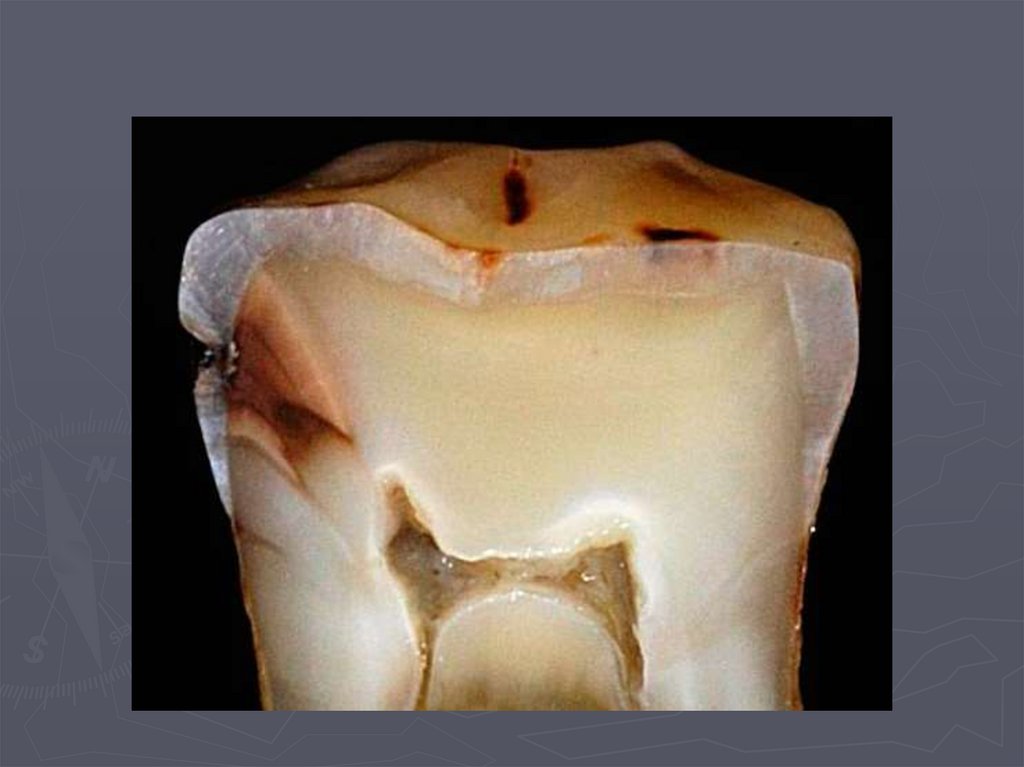

49. Глубокий кариес

► во временных и постоянных зубах с

несформированными корнями практически не

диагностируется.

Клинически глубокий кариес:

► наблюдается в постоянных зубах со сформированными

корнями;

► боли от механических ,химических, температурных

раздражителей;

► после устранения причины боль исчезает;

► кариозная полость значительных размеров;

► дентин размягченный, пигментированный;

► зондирование болезненно по дну.